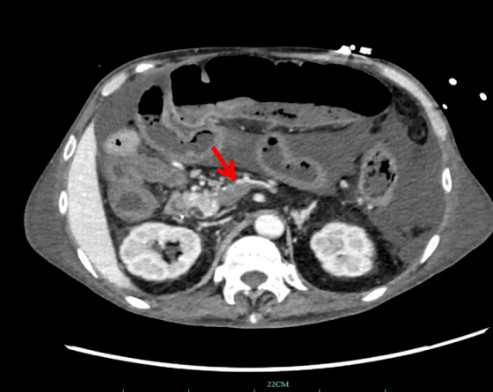

1.2 辅助检查患者神志清,精神软,禁食,睡眠差,发病来体重下降20 kg,体温36.7℃,脉搏67次/min,呼吸16次/min,血压89/56 mmHg (1 mmHg=0.133 kPa)。肺部CT(HR)平扫:两肺散在渗出,两侧胸腔积液伴两肺部分萎陷;腹膜及腹水(彩超):腹腔积液。超声心动图示:左房增大、心律不齐。双下肢静脉彩色多普勒超声:双下肢深静脉血流通畅。肠系膜动静脉CTA:肠系膜上静脉显示欠清,其属支血栓形成考虑(图 1)。系膜网膜模糊浑浊,腹盆腔积液,胃肠壁稍水肿。腹膜后、肠系膜区多发淋巴结稍大,腹盆壁皮下水肿(图 2)。

| 图 1 患者入院时肠系膜CTA |